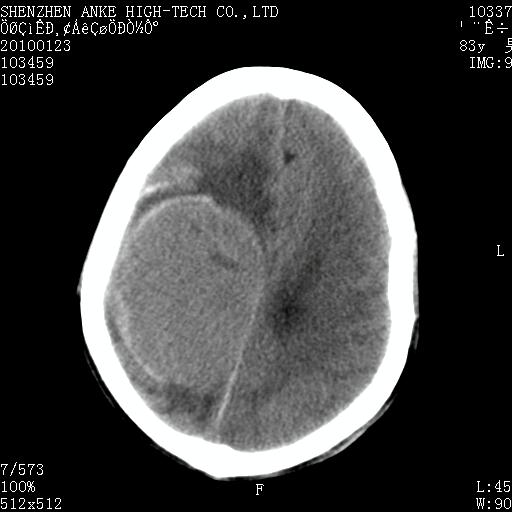

患者:男,83岁,突发意思不清2天。原有脑梗塞病史。

肿瘤卒中,考虑恶性,依次淋巴瘤、转移瘤、恶性脑膜瘤、胶质母等,建议mri。

肿瘤卒中,考虑恶性脑膜瘤可能性大。

脑膜瘤多见于老年女性,与雌激素水平有关。本例虽为老年男性,但是本例还是考虑脑膜瘤的可能性大。

镰旁脑膜瘤卒中